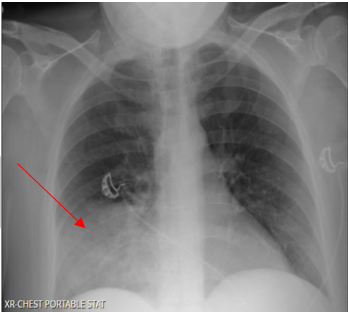

Laboratory testing was notable for elevated WBC, 19.5 (4.0-10.5 K/UL), neutrophils 78.3%, lymphocytes 7.7%, Monocytes 13.5%, eosinophils 0.2%, basophils 0.3%, Procalcitonin 1.46 ng/ml (reference range :< 0.25 ng/ml), SARS-COV 2 was negative. Blood culture, sputum culture, urine strep and legionella urine Antigens were negative, and the upper respiratory PCR panel was negative. MRSA PCR negative. Chest-X ray revealed a consolidation within the right lower lung field, while the CT Chest Angiography showed no evidence of acute pulmonary embolus. Furthermore, there was a progression of consolidative changes in the right middle lobe, traces of right pleural effusion, mild bilateral lower lobe atelectasis, and rounded opacity in the posterior left lower lobe measuring 10 mm. On the same note, there was rounded opacity in the right lower lobe measuring 13 mm, which was a new finding from the prior imaging study, and prominent mediastinal and hilar lymph nodes with the right paratracheal lymph node measuring 13 mm and right hilar lymph node measuring 19 mm (Figure 3 and 4).

Figure 3. Portable Chest X-ray on Hospital admission showing consolidation in the right lower lung field.